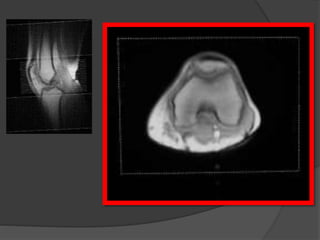

Rx

Cartilago articular

• Rx= imagen indirecta

• RM = buen contraste y visualización

de tejidos circundantes

• RM alta resolución= detecta cambios

morfológicos en el cartílago